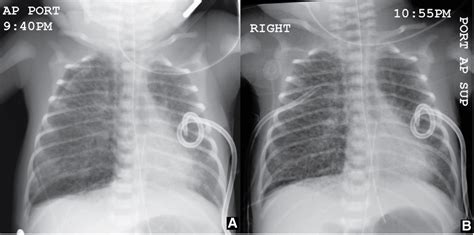

Okay, let’s get down to the nitty-gritty of how pulmonary interstitial emphysema radiology actually looks on a chest X-ray . This is often the first line of imaging used. When a radiologist looks at an X-ray of a patient with PIE, they’re scanning for specific patterns. One of the classic signs is the appearance of linear lucencies, which are essentially dark lines on the X-ray film. These lines represent air tracking within the interstitial tissues. Imagine tiny air bubbles or streaks running through the lung tissue, separate from the normal branching pattern of airways and blood vessels. Another key finding can be a ‘cystic’ or ‘bubble-like’ appearance, where larger pockets of air have accumulated in the interstitial space, sometimes looking like clusters of small balloons. You might also see signs of lung hyperinflation, where the lungs appear larger than normal, often because air is getting trapped. Sometimes, PIE can lead to a condition called pneumothorax, which is air in the space outside the lung, between the lung and the chest wall. This is a serious complication and appears as a dark space separating the lung from the chest wall on the X-ray. The diaphragm might also appear flattened due to the hyperinflation. It’s important to note that PIE can sometimes be subtle on an X-ray, especially in its early stages or if it’s mild. The radiologist has to be really vigilant and compare the current X-ray with previous ones if available to spot any changes. They’re looking for deviations from the normal, healthy lung pattern, and PIE creates a very distinct set of deviations. It’s a diagnostic puzzle, and the X-ray provides the primary pieces to solve it. The clarity and detail needed to spot these subtle linear lucencies and cystic changes are what make the radiologist’s expertise so vital in interpreting these seemingly simple images.